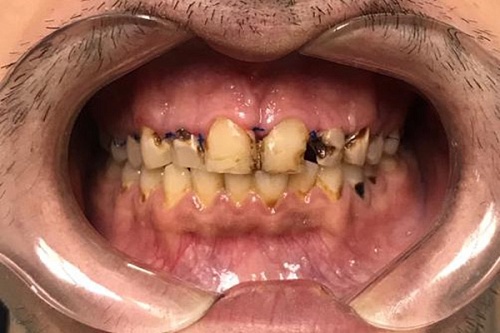

Изменения тканей, которые окружают корни зубов, к сожалению, неизбежны и с возрастом наблюдаются у всех, однако в разном объеме. Так, на развитие пародонтита влияет болезнетворная микрофлора полости рта, которая есть у каждого из нас, но на мы в силах повлиять на ее количество.

Сохранить зубы и пародонт помогает правильная гигиена полости рта дома и в кресле стоматолога, а также своевременное протезирование и имплантация, которые замещают удаленные зубы и равномерно распределяют жевательную нагрузку, не позволяя костной ткани атрофироваться.

Таким образом, по мнению стоматологов, риск возникновения болезней десен на 80% зависит от сознательности самого пациента.